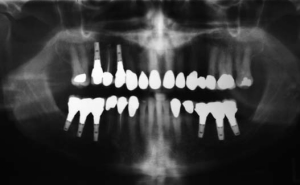

Interdisciplinary Treatment Planning With Implants

figure 26

People in our society can expect to live longer than in any previous generation. Many choose to avoid loosing their teeth and refuse to use removable dental prostheses. They present with increasingly complex dental histories. For these reasons, dentists in the mainstream of dental care are increasingly practicing the skills of interdisciplinary treatment planning in … Read more